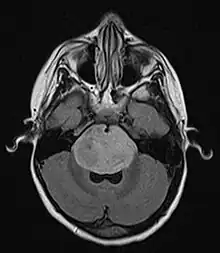

| Brain stem glioma. MRI axial, with contrast | |

Neuroimaging, such as MRI, is the main diagnostic tool for brain stem gliomas. In very rare cases, surgery and biopsy are performed.